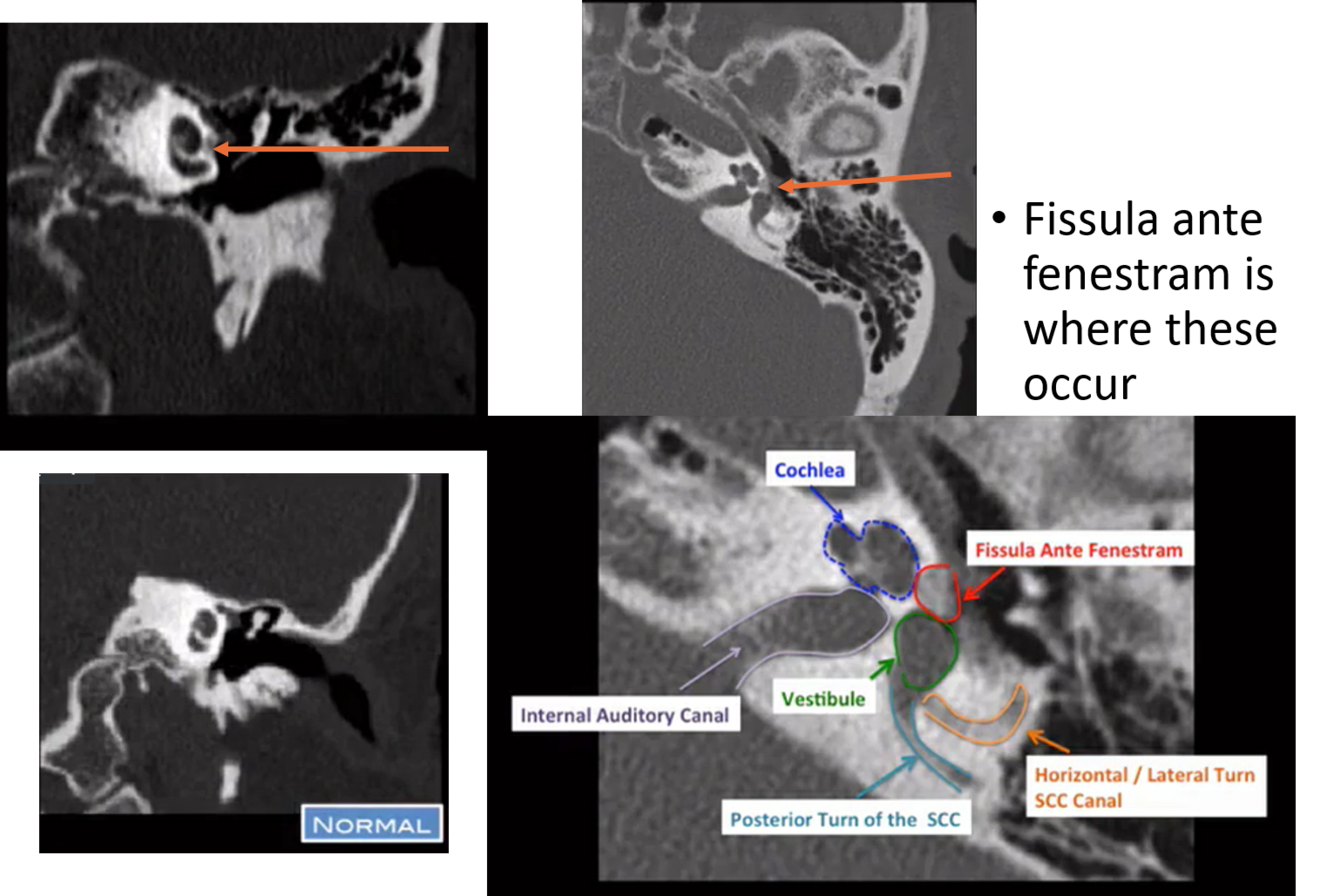

otosclerosis (otospongiosis)

demineralization at the fissula ante fenestram

in otosclerosis where does demineralization typically occur?

fissula ante fenestram